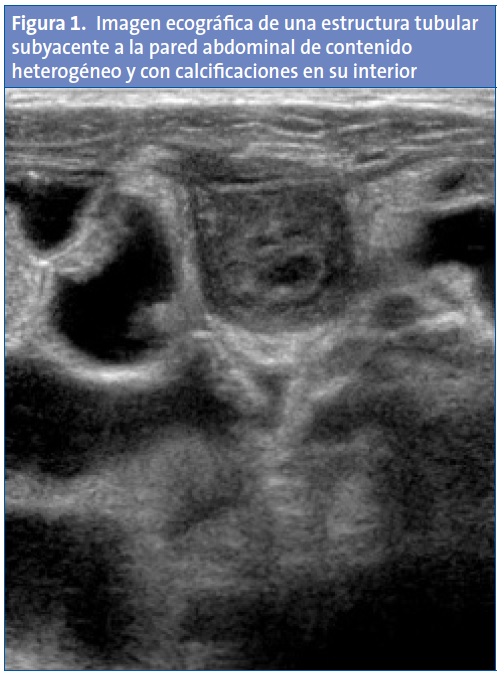

Se realiza una tira reactiva de orina que es normal y, ante la sospecha de un cuadro infeccioso intraabdominal, se realiza una ecografía abdominal en el centro de salud en la que se aprecia en la región umbilical, inmediatamente por debajo de la pared abdominal y en dudosa comunicación con la vejiga, una imagen tubular lobulada de unos 5x2 cm, heterogénea, con flujo Doppler periférico y áreas hiperecogénicas puntiformes compatibles con calcificaciones (Figs. 1 y 2).

Con estos datos clínicos y ecográficos, se sospecha que podría tratarse de un quiste de uraco complicado, por lo que se deriva a Urgencias del hospital de referencia, donde se realiza una analítica, en la que destaca un hemograma con leucocitosis de 16 860/mm3, neutrofilia del 80%, trombocitosis de 473 000/mm3 y proteína C reactiva de 56,8 mg/l, se realizan también una ecografía y una tomografía computarizada (TC) que confirman la sospecha diagnóstica.